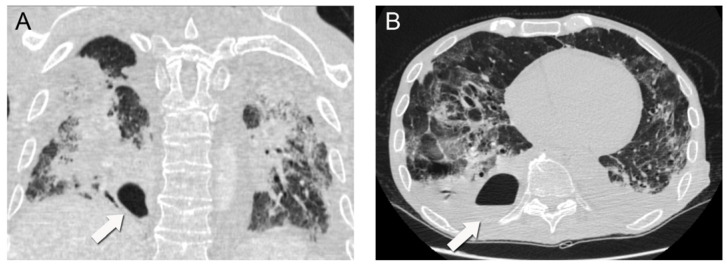

A repeat chest CT scan demonstrated multiple converging consolidated lesions in both lungs with scattered areas of ground glass. Most notably, in the posterior basal segment of his right lower lung lobe, an intraparenchymal thin-walled cavity measuring 7 × 4 cm2 in diameter was observed. The presence of an air-fluid level was indicative of a pulmonary abscess associated with the previous areas of dense consolidation (Figure 2). It was hypothesized that the pulmonary abscess was possibly associated with a bacterial superinfection caused by the COVID-19 disease. Due to unstable respiratory conditions, bronchoscopy was not performed. However, direct cultures were obtained via thoracentesis under ultrasound guidance and fluid aspiration. Both blood and aspirated fluid cultures failed to identify a causative microorganism.

Figure 2.

Subsequent chest CT scan demonstrating a 7 × 4 cm2 intraparenchymal abscess (arrows) with an air-fluid level in the posterior basal segment of the right lower lung lobe (coronal (A), axial (B)).